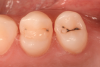

The placement of posterior restorations may lead to postoperative sensitivity.19 Two main characteristics that are important to consider when dealing with posterior restorations are the configuration factor (C-factor) of the preparation and the amount of dentin involved when compared with the amount of enamel. A preparation's C-factor refers to the ratio of bonded to unbonded surfaces. For example, Class I preparations have a C-factor of 5, and Class II preparations have a C-factor of 2. For preparations in which the amount of dentin is greater than the amount of enamel, a self-etch approach is advised because it may reduce postoperative sensitivity. Universal adhesives with functional monomers are able to chemically bond to dentin, which exists in greater amounts in posterior teeth.20 Using them in a selective enamel etching approach can improve the marginal seal that is obtained. In the clinical case described here, two premolars were restored using a universal adhesive in a selective enamel etching approach. The patient presented with primary and a secondary caries on teeth Nos. 12 and 13 (Figure 1). After isolation with a rubber dam (Figure 2), the teeth were prepared using a cylindrical bur, and the enamel was selectively etched with phosphoric acid (Figure 3). A universal adhesive was then applied, and composite was placed to restore the tooth using a cusp-by-cusp modeling approach (Figure 4 and Figure 5).

(3.) The enamel was selectively etched prior to the application of a universal adhesive.

Figure 3

(4.) Posttreatment photograph of the completed Class I restorations.

Figure 4